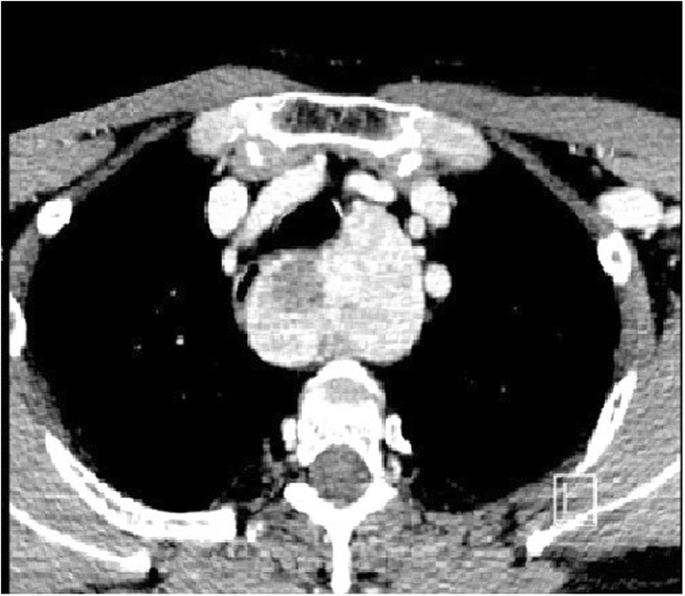

As already mentioned in another work [3] the extension of the goiter under the aortic arch (Fig. 1), documented at the CT, was significantly correlated (p = 0,001) with a cervicotomy associated with partial sternotomy. This evidence has already been widely validated and described in Literature and it is now considered one of the main features for the choice of surgical treatment in substernal goiters [5, 6, 9, 10,11,12,13, 16, 32].

Thoracic CT was performed in all 44 patients: an extension above aortic arch was found in 41 cases (93.18%) and below aortic arch in 3 patients (6.82%).

The extension of the goiter below the aortic arch appeared to be a predictive value in the choice of surgical treatment (p = 0.0001), Table 1.